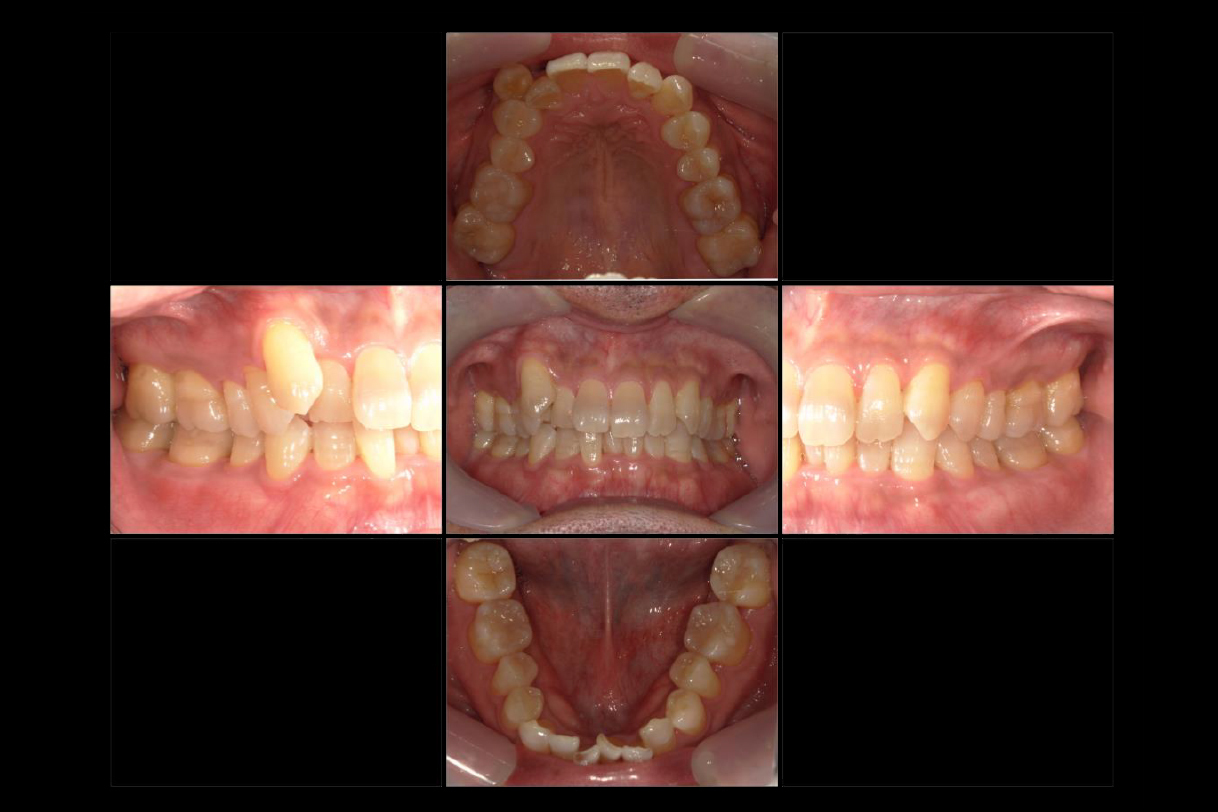

2022年9月

浜松市中区の症例紹介 マウスピース矯正

2025年9月

初診時年齢:40代男性

治療:全体矯正

治療法:マウスピース型矯正装置(インビザライン)

治療期間:3年

費用:902,000円(税込)

リスク・副作用:装置装着による違和感、歯の移動時の痛み